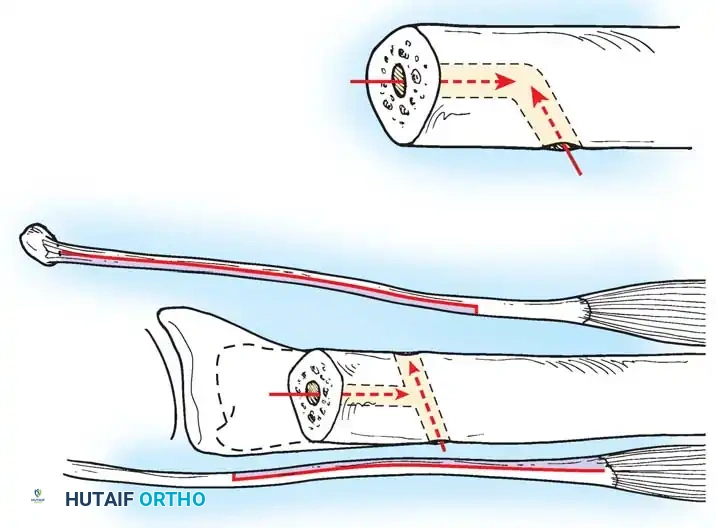

In chronic settings where the TFCC is irreparable, anatomic ligament reconstruction using a tendon autograft (e.g., palmaris longus) is indicated. The graft is routed through the distal radius and ulnar fovea to recreate the dorsal and volar radioulnar ligaments.

Tendon graft routing through osseous tunnels in the radius and ulna for anatomic reconstruction of the DRUJ ligaments.